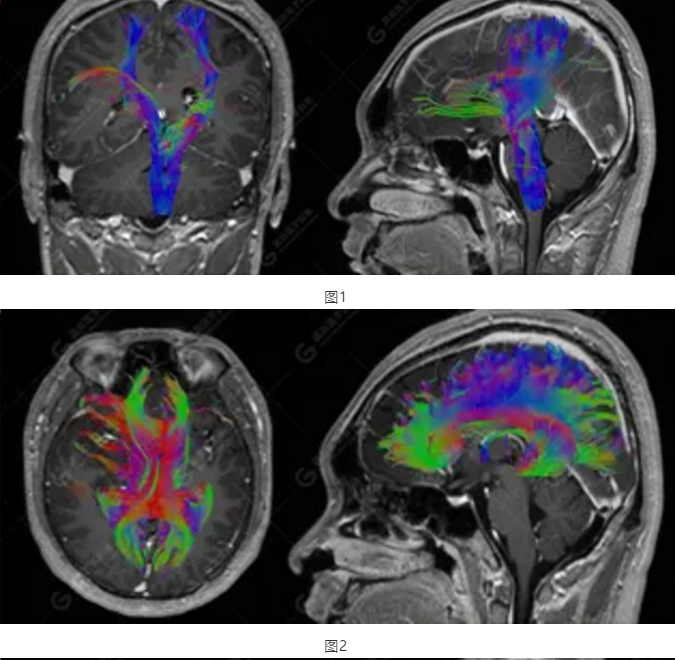

以上為DTI成像,圖1為皮質(zhì)脊髓束,圖2為胼胝體束,圖3為扣帶回束,圖4為額枕束。DTI成像示右側(cè)額枕束前部明顯受壓、部分未見(jiàn)顯示;胼胝體束、雙側(cè)扣帶束、皮質(zhì)脊髓束及左側(cè)額枕束形態(tài)可,纖維束未見(jiàn)明顯破壞,未見(jiàn)明顯稀疏減少。